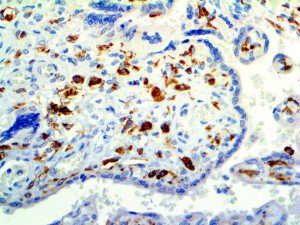

It is the ICU physician who is most likely to witness one of the deadliest manifestations of the abnormal immunological response, the cytokine storm syndrome (CSS). This response is also referred to by some as the cytokine release syndrome (CRS). CSS is characterized by continuous activation and expansion of macrophage and lymphocyte populations, which secrete large amounts of cytokines, causing the cytokine storm. This massive cytokine release is akin to hemophagocytic lymphohistiocytosis (HLH) disease, a syndrome characterized by initial unchecked and persistent activation of cytotoxic T lymphocytes and NK cells.

Clinical and laboratory manifestations of HLH include fever, enlarged liver and/or spleen, neurologic dysfunction, coagulopathy, liver dysfunction, cytopenias (i.e., low levels of erythrocytes, leukocytes, and/or platelets), hypertriglyceridemia, hyperferritinemia, hemophagocytosis, and eventually diminished NK cell activity as the immune system becomes progressively paralyzed. HLH can be familial (primary HLH) or secondary to another disease process (sHLH), such as rheumatic disease, in which it is referred to as macrophage activation syndrome (MAS, characterized by elevated ferritin).